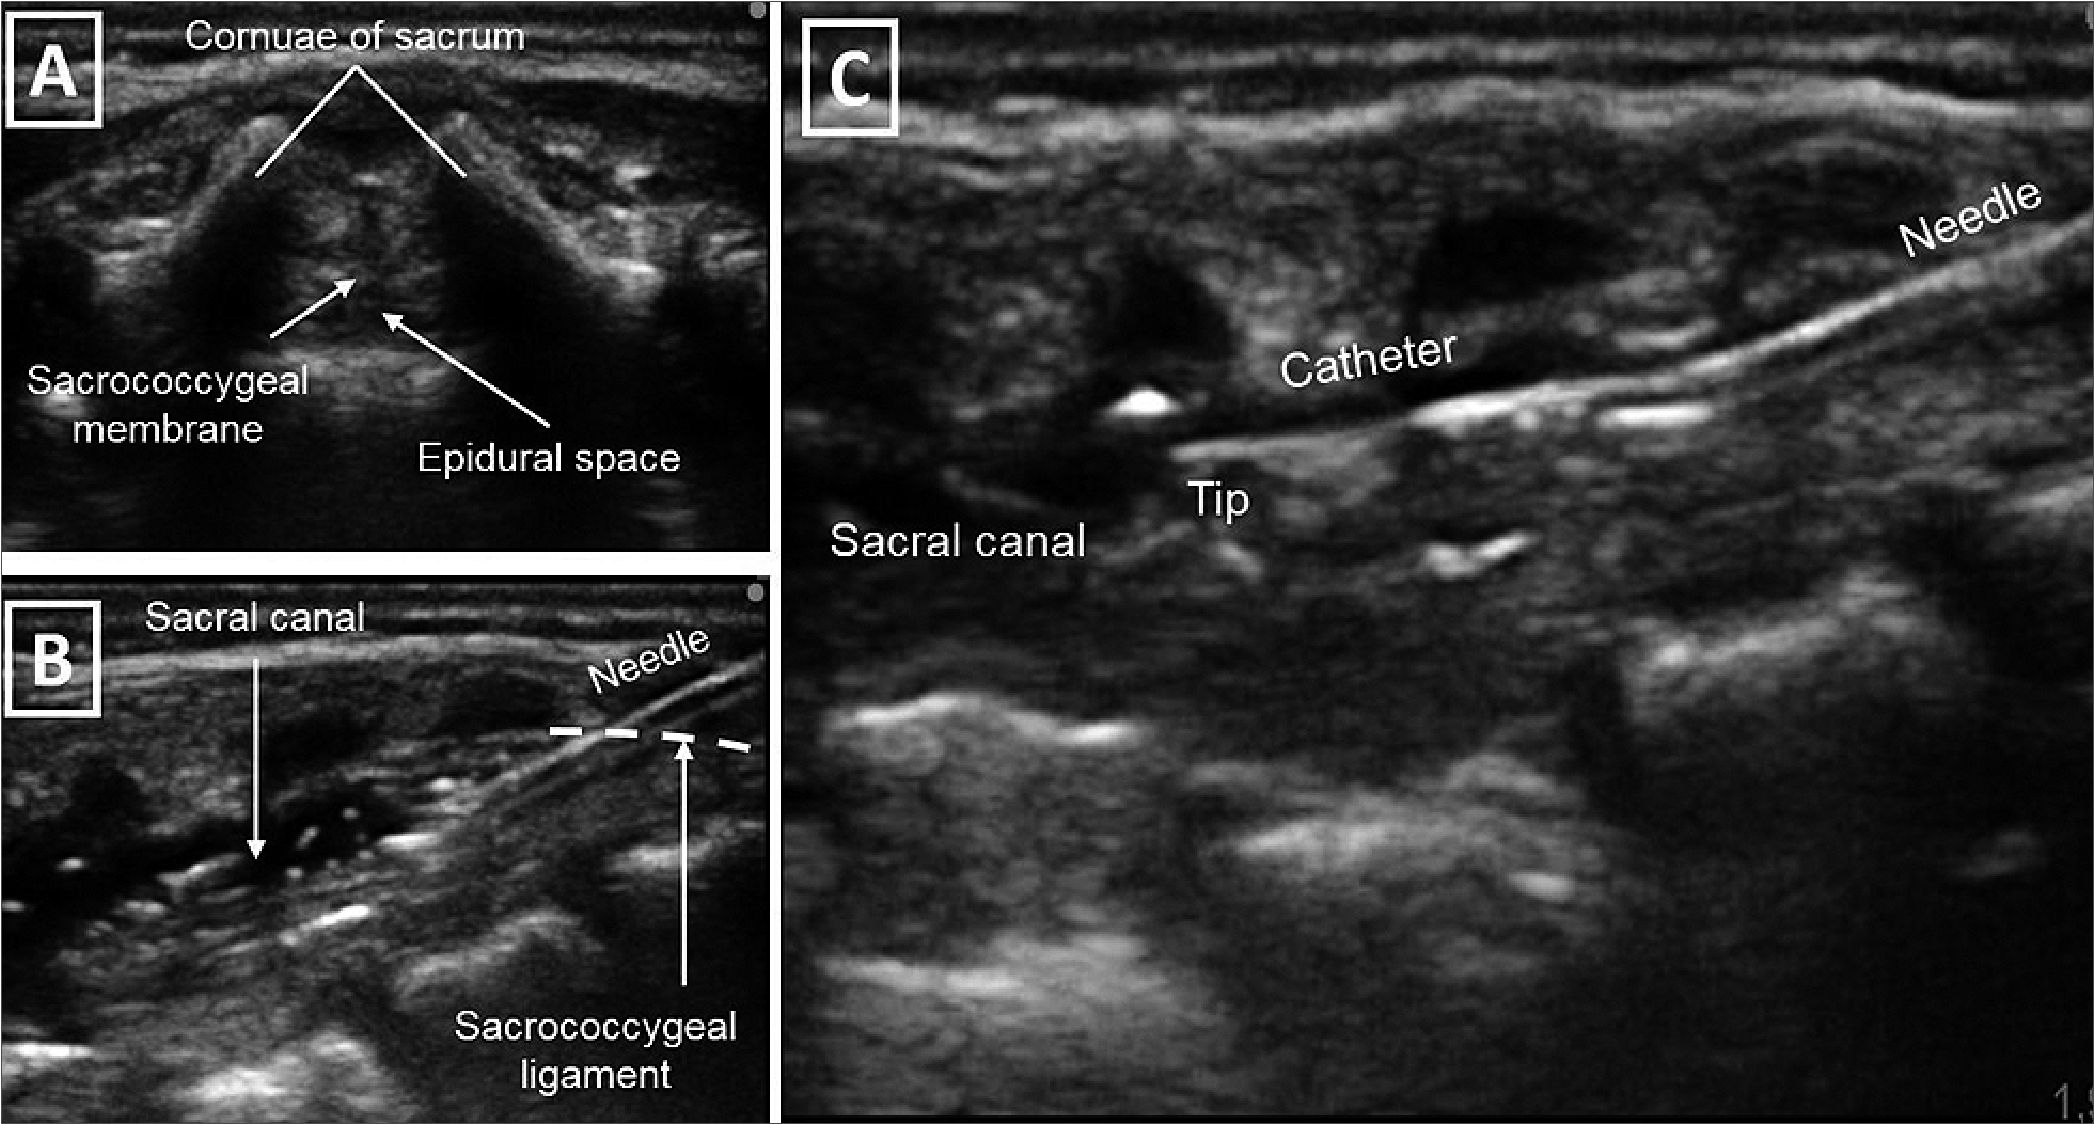

A term new-born weighing 2,800 grams was delivered vaginally at 38 weeks. He exhibited adequate adaptation but was diagnosed with multiple conditions including bladder exstrophy, pubic diastasis, corpus cavernosum malunion, and epispadias. Further extension studies were conducted, which included an echocardiogram revealing a persistent ductus arteriosus, satisfactory biventricular function, and no signs of pulmonary hypertension. An abdominal ultrasound confirmed the presence of left renal agenesis. Complete blood counts and renal function were found to be within normal limits. At 13 days of age, weighing 2.8 kg, the patient was admitted to the operating room for bladder exstrophy correction. During the procedure, the patient received basic monitoring, including inhaled sevoflurane at a concentration of 6 vol% and intravenous fentanyl at a dosage of 4 mcg/kg for induction. Orotracheal intubation was performed using a 3.0 uncuffed tube. Invasive monitoring was established through the placement of an ultrasound-guided right internal jugular central venous catheter and a left radial arterial line. With the patient positioned in left lateral decubitus, and following strict antiseptic technique, a high-frequency linear transducer was used to guide the procedure. A 20 g Touhy needle was inserted sacrococcygeally, and a peridural catheter was advanced up to t10-t11 level without any complications (Figure 1). Anaesthetic maintenance included a bolus of 1.5 cc/ kg of 0.1% bupivacaine through the catheter, and sevoflurane at 1 mac. A dose of Cisatracurium was used for neuromuscular relaxation, as was needed to aid the introduction of the bladder into the abdominal cavity and for approximation of the pubic rami. Throughout the 5-hour duration of the procedure, 10 cc of bleeding was obtained; urine output was not measured. Fluid resuscitation was guided by haemodynamic parameters such as heart rate, blood pressure and subjective variability of arterial line morphology. We administered 0.9% saline and 5% albumin, with which a neutral fluid balance was achieved. For transitional analgesia, a second bolus of 1 cc/kg of 0.1% bupivacaine was administered through the epidural catheter, along with 2 mcg/kg of fentanyl. At the end of the procedure, the patient exhibited spontaneous breathing with satisfactory ventilator mechanics, was normothermic, normoglycemic and with adequate acid-base equilibrium. Based on these favourable conditions, the decision was made to extubate the patient in the operating room. His lower limbs were immobilized, and he was transferred to the neonatal intensive care unit.

Figure 1. (A) Transversal cross section of the neural axis through the sacral hiatus; (B) Longitudinal cross section of the neuro axis. The needle inserted in plane through sacrococcygeal ligament to the sacral canal; (C) Ultrasound guided insertion of the epidural catheter with direct visualization of the tip. Source: Authors.

In our case, employing ultrasound guidance during the caudal catheter insertion, enabled us to precisely position the catheter tip at the intended intervertebral level. The accurate placement facilitated effective pain management without the need for opioids, promoted tolerance to lower limb immobilization, and allowed for the early initiation of oral intake. Additionally, the ultrasound-guided localization of the catheter tip at the desired intervertebral level potentially contributed to the patient requiring lower infusion rates of anaesthesia, thereby minimizing the occurrence of secondary hemodynamic changes.